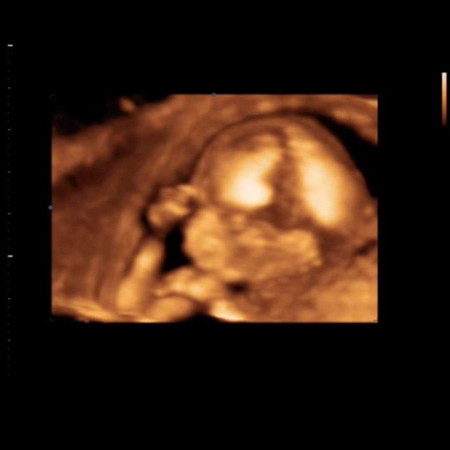

น้องตัวเล้กไปไหมค่ะ

ซาวตอน 16w น้องมีขนาด 10.86 cm น้ำหนัก 146กรัม